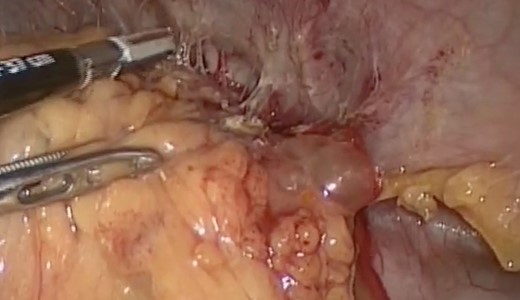

Intraoperative findings included extensive inflammation involving the inferior half of the spleen, the splenic flexure of the colon and the distal pancreas, as well as the abscess in question which contained approximately 10 cc of purulent material (Figs 3 and 4). The final surgical specimen included the entire spleen and the histologic report of pancreatic tissue compromised by the abscess. The patient was transferred to the surgical ICU for 24 hours. The following day, the blood cultures taken on admission grew an extended spectrum beta-lactamase producing Escherichia coli resistant to carbanemic agents and sensitive to tigecycline. The antibiotic regimen was modified accordingly, and after 7 days the patient was discharged symptom-free and with a plan to complete 15 days of tigecycline at home.

Inflammatory tissue dissection and drainage of the splenic abscess.